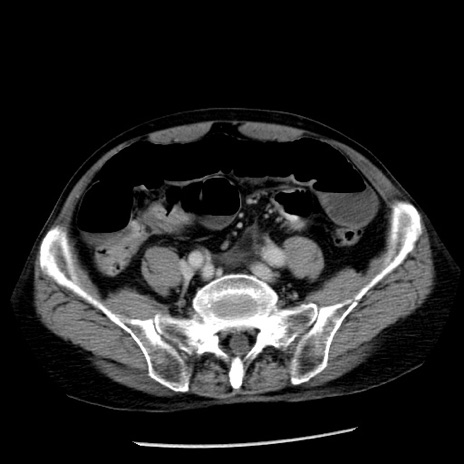

冠状断像

【症例】80歳代男性

【主訴】嘔吐

【現病歴】昨晩2回嘔吐あり、今朝になっても嘔吐あり。来院。

【既往歴】胃潰瘍

【身体所見】意識清明、BT 37.6℃、BP 166/95mmHg、HR 100bpm、SpO2 97%、腹部:平坦・軟、腸蠕動音聴取良好、圧痛なし。

【データ】WBC 21900、CRP 1.46